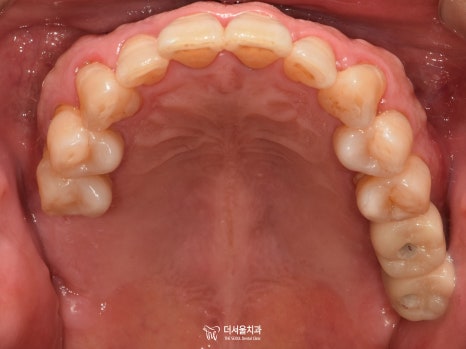

3) 교합면

발치를 하셨기 때문에 텅 비어 있는 곳이 많았습니다.

하악 전치부 쪽이 심각한 것으로 판단이 되네요.

스케일링을 통해 쌓여있던 치석과 이물질들을

깨끗하게 제거를 해주었습니다.

크라운까지 올려드렸습니다.

더 건강하고 멋있는 미소를 갖게 되셨네요ㅎㅎ